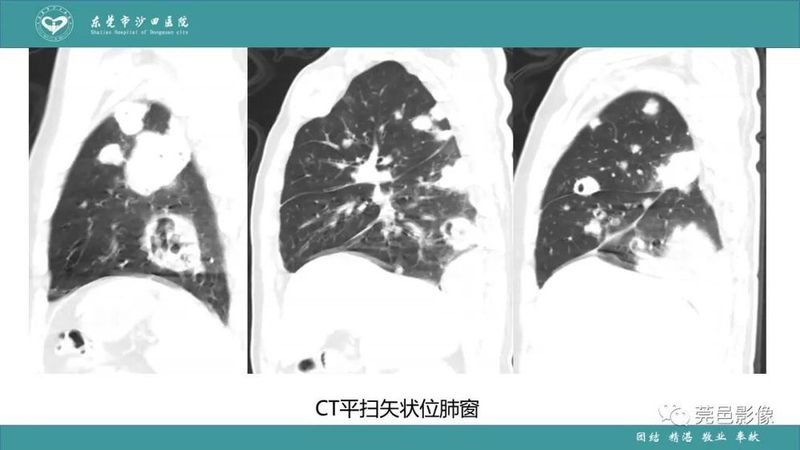

「肺炎克雷伯杆菌肺炎」影像学诊断+鉴别诊断